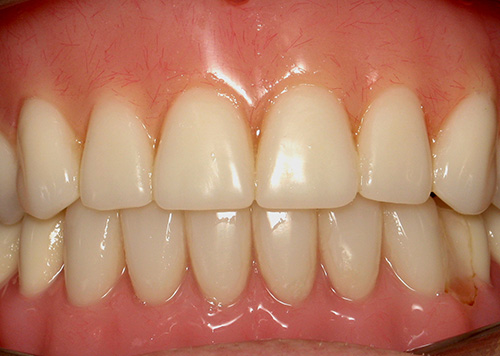

Smile Gallery

Orthodontic Treatment X-ray - After